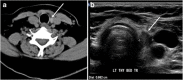

Focal and diffuse thyroid abnormalities are commonly encountered during the interpretation of computed tomography (CT) exams performed for various clinical purposes. These findings can often lead to a diagnostic dilemma, as the CT reflects the nonspecific appearances. Ultrasound (US) examination has a superior spatial resolution and is considered the modality of choice for thyroid evaluation. Nevertheless, CT detects incidental thyroid nodules (ITNs) and plays an important role in the evaluation of thyroid cancer. In this pictorial review, we cover a wide spectrum of common and uncommon, incidental and non-incidental thyroid findings from CT scans. We also discuss the most common incidental thyroid findings, best practices for their evaluation, and recommendations for their management. In addition, we explore the role of imaging in the assessment of thyroid carcinoma (before and after treatment) and preoperative thyroid goiter, as well as localization of ectopic and congenital thyroid tissue.

Teaching points: • Thyroid disorders tend to have non-specific CT appearances. • ITNs are common on neck CT. • ITN management depends on nodule size, age, health status, lymphadenopathy, and invasion. • CT is used in assessment of cancer extension, mass effect, invasion, and recurrence. • CT plays a role in preoperative planning in patients with symptomatic goiter.